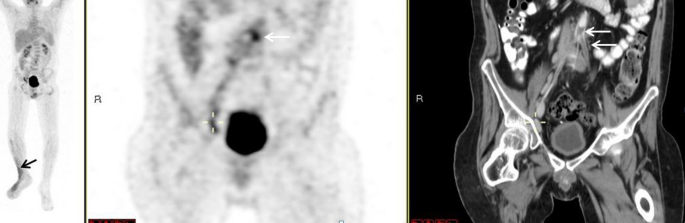

The presence of arterial thrombus

Evidence of a 2 cm thrombus along the superior mesenteric artery was demonstrated in the PET/CT of a patient who had salmonella bacteremia. Heightened tracer uptake presented in that area, with an SUVmax of 2.3. In the patient with Behçet's, PET/CT highlighted a filling defect along the bifurcation of the iliac arteries. Enhancement was increased in the regions both proximally and distally, which extended into the bilateral iliac arteries (Fig. 4).

FDG-PET/CT: FDG-PET/CT: maximum intensity projection (MIP) (a) a representative PET (b) and CT (c) coronal slices. A 37-year-old man with Behçet's disease. PET demonstrated increased uptake along the filling defect in the aorta at the bifurcation extending to the iliac arteries (white arrows, b, c) and increased uptake in the soft tissues of the Rt leg (black arrow, a).